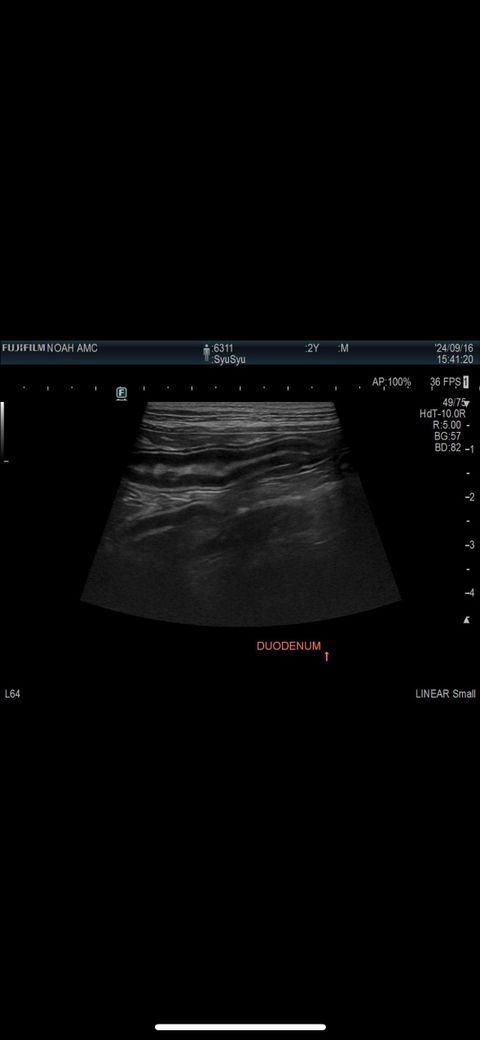

첨부된 사진에는 결장이 포함된 사진이 단한장도 없고, 있다고 하여도 초음파 검사는 정지사진으로는 별 진단적 의미가 없습니다. 초음파를 직접 본 영상의의 소견이 가장 중요합니다.